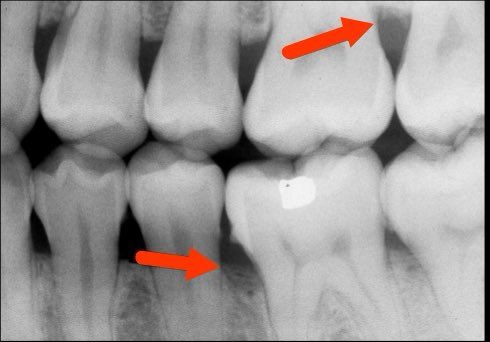

-التهاب اللثة العميق (متوسط) (المرحلة ٣):

- بعض علامات التهاب اللثة الخارجية (ليس بالضرورة تكون موجودة)

-تآكل لمستوى اكثر في العظم الداعم

-نزوح في اللثة الخارجية (النسيج المحيط بالأسنان) (أحيانا)

-بدء حركة الأسنان بدرجة بسيطة

-يكتشف احيانا بالصدفة عند اخذ أشعة الأسنان(٤)=